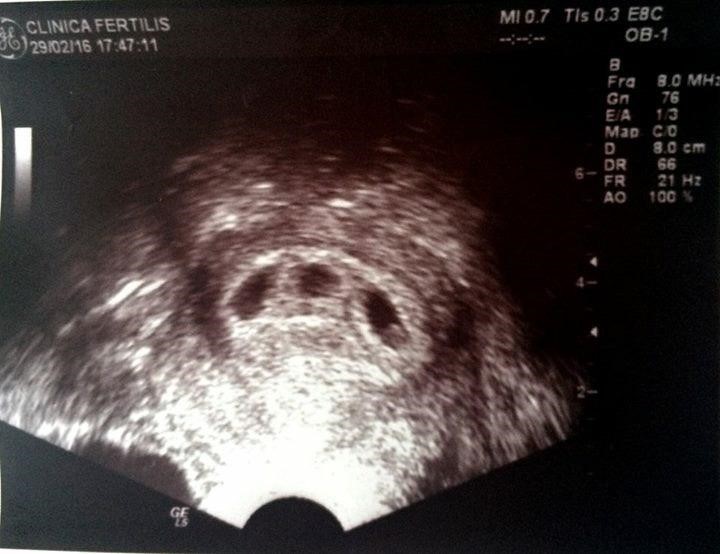

O positivo veio. No ultrassom, um saco gestacional. Depois dois. Depois três. O médico respirou fundo e disse “temos um problema”. O marido não hesitou: “Problema nenhum.” Ela só precisou de uma resposta: “Os corações estão batendo?” Estavam. Todos eles.